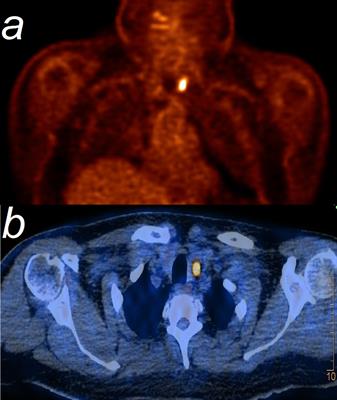

Case Report

Published on 20 Dec 2022

in Nuclear Medicine